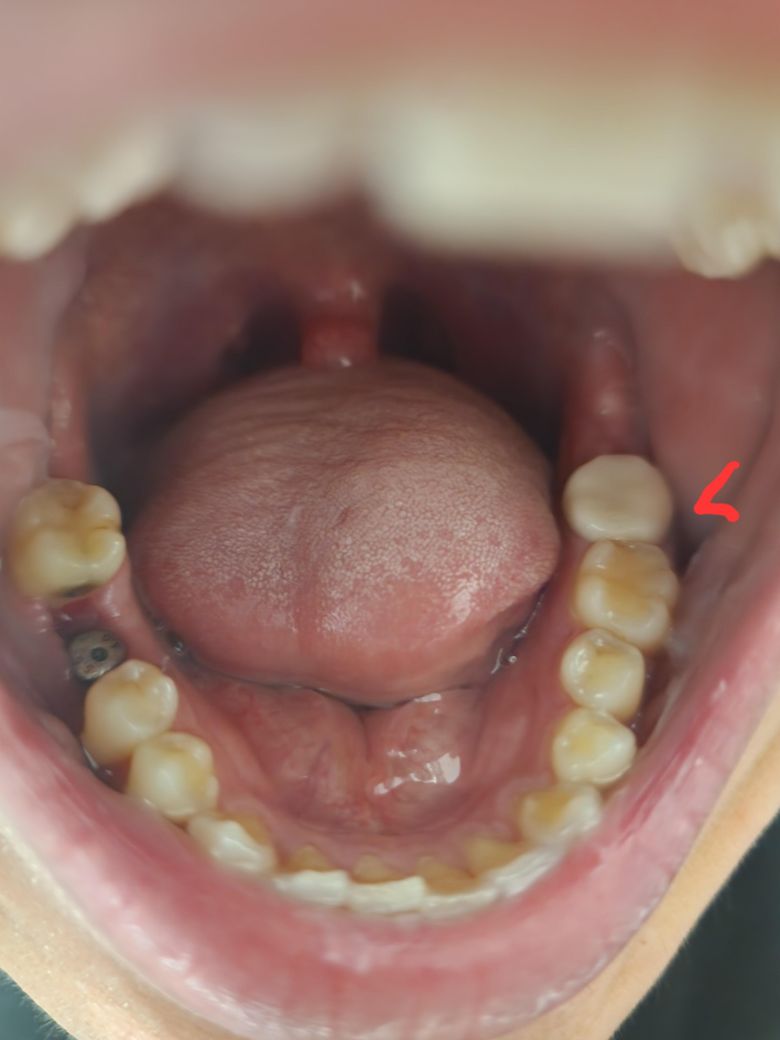

올해1월에 왼쪽 아래 맨안쪽 어금니 크라운치료한게 문제가있어 5월20일날 크라운재제작을 위해 현재 임시치아 부착상태입니다.그런데 사진에서 보시다싶이 왼쪽 아래 맨안쪽 임시치아가 위쪽 치아랑 맞물리지 않아 미세하게 틈이 있습니다ㅜㅜ그래서 그런지 입을 다물때 반대편치아가 높은 느낌이 있구요...인터넷 검색해보면 저런식의 내용이 나오는데 괜찮은거 맞나요?다음주 목요일이 최종크라운 씌우는날인데 최종크라운을 끼게 되면 사진에서 보시다싶이 위아래 치아가 맞물리게 될까요?긴글 읽어주셔 너무 감사드리구 제발 확실한 답변 부탁드립니다.존경하는 의사님들(__) ㅜㅜ

• 1번 째 사진

• 2번 째 사진

• 3번 째 사진